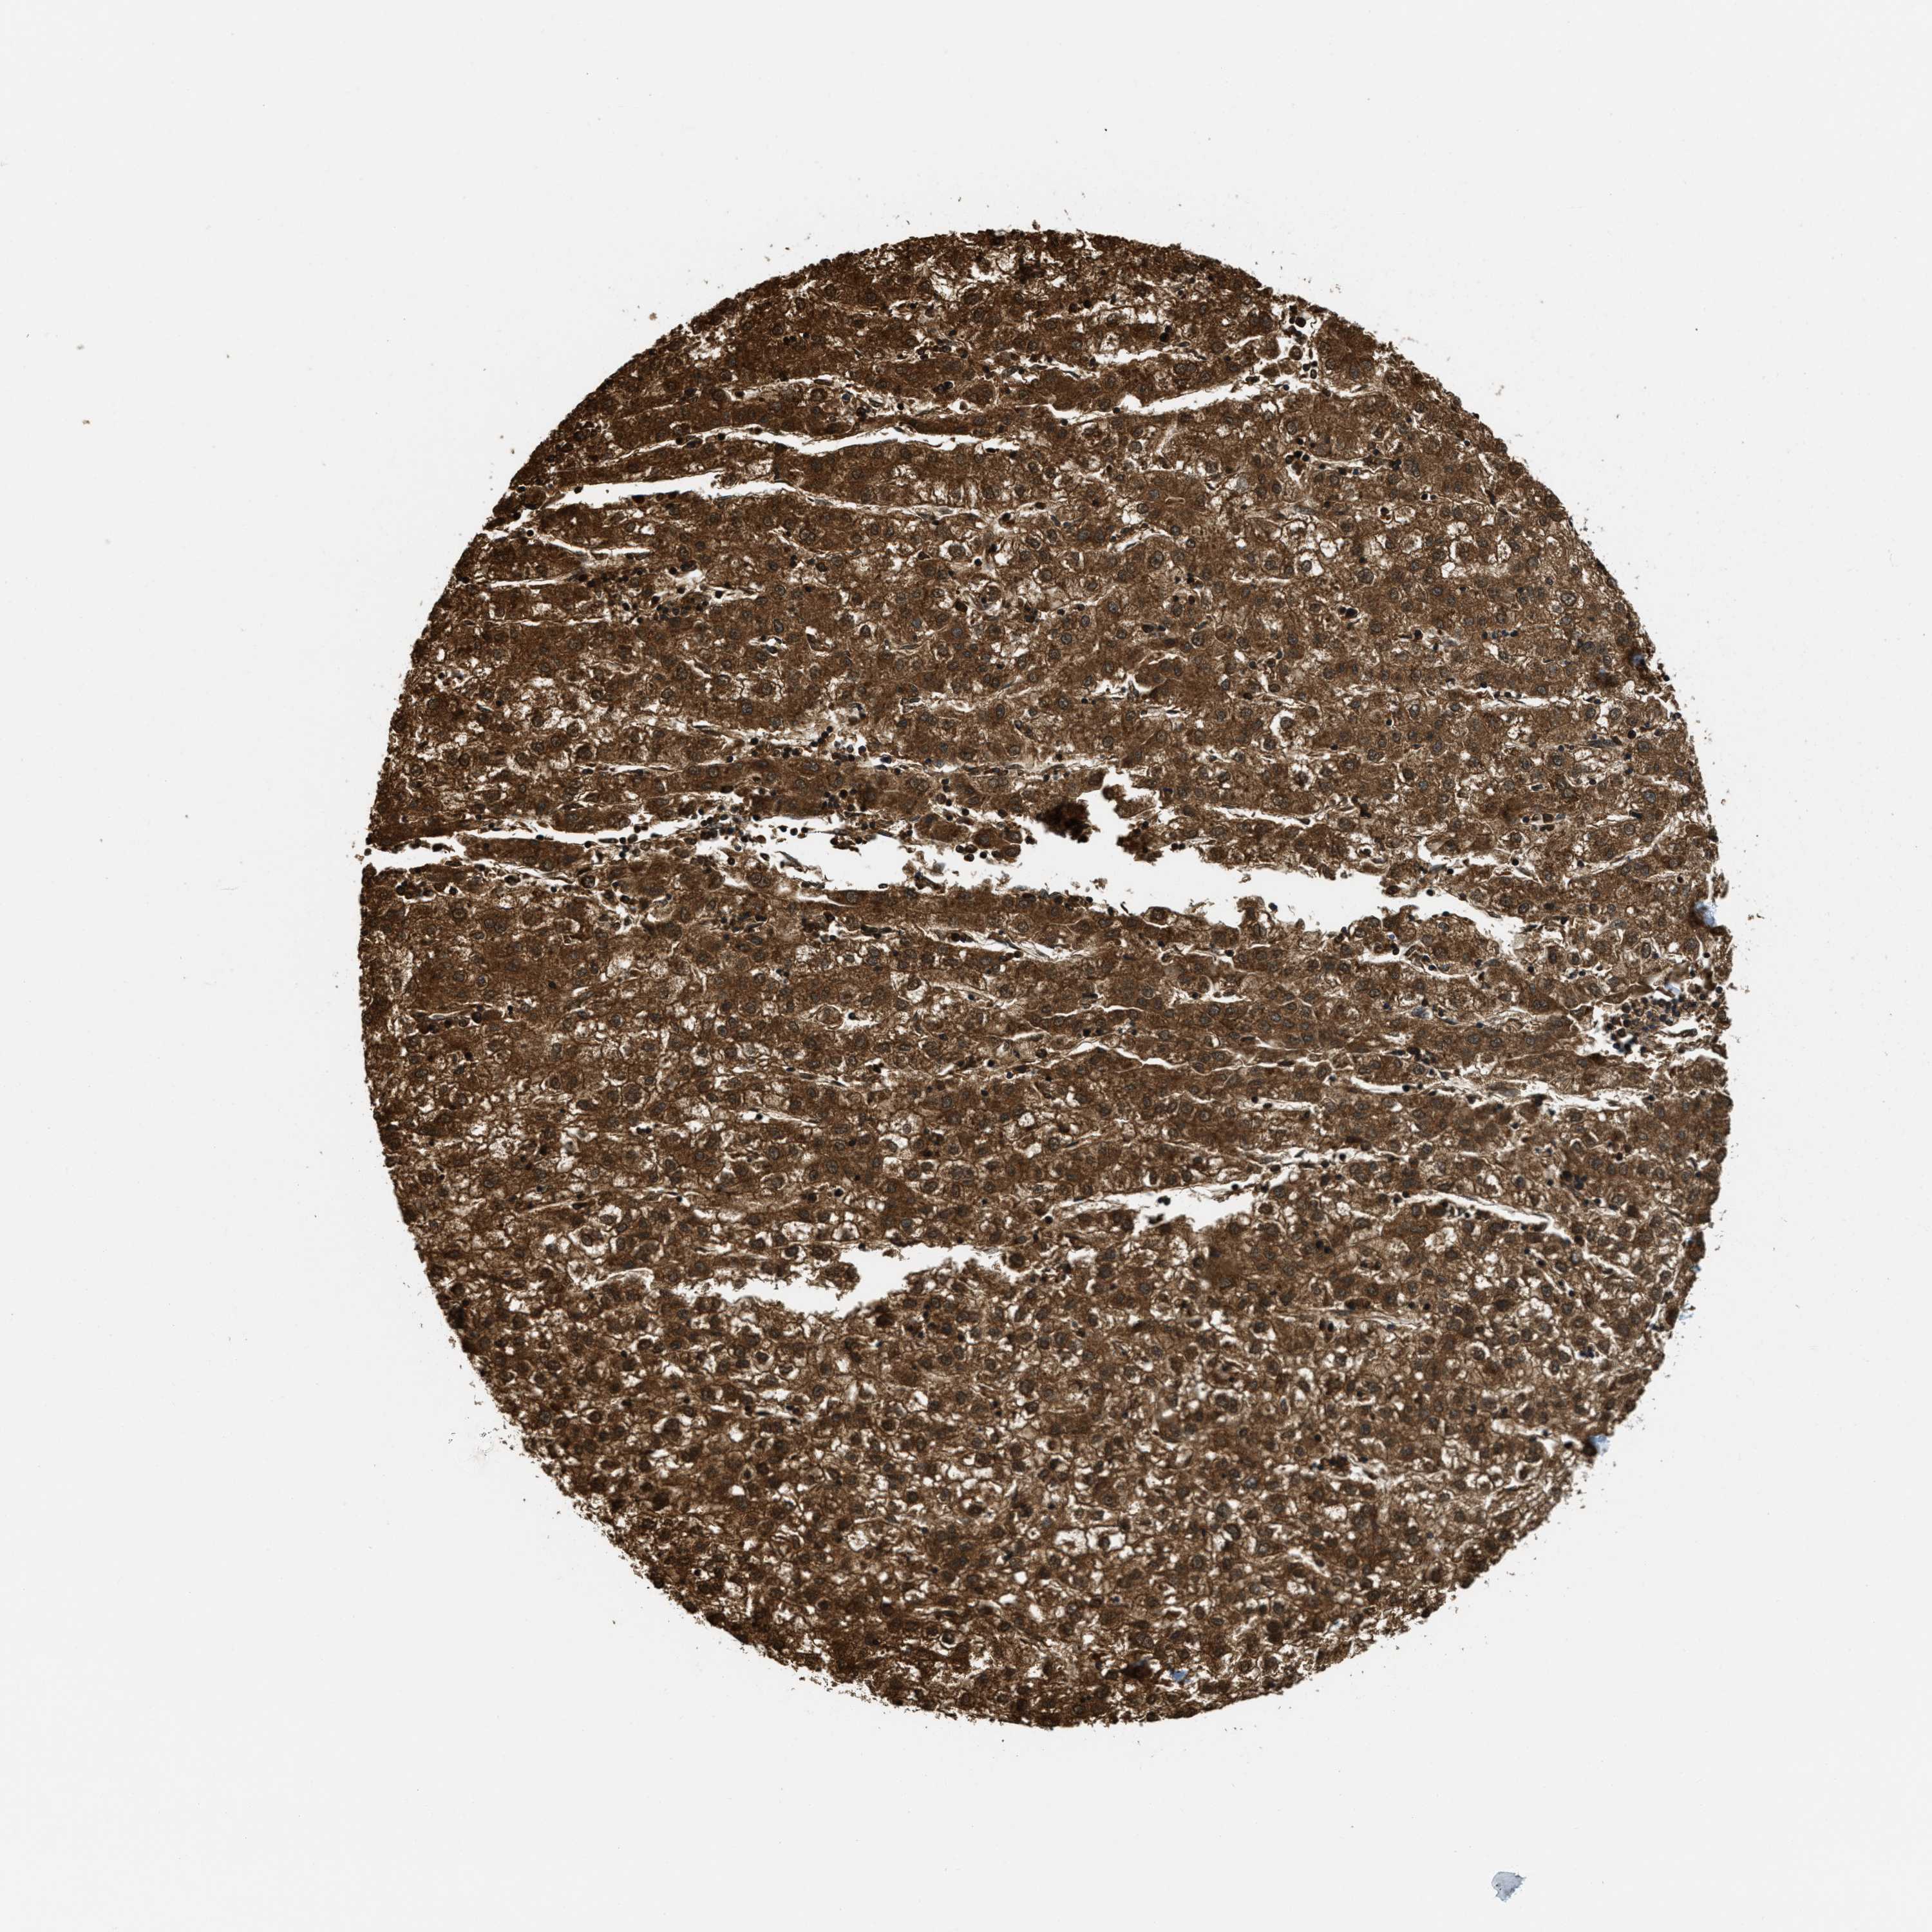

LIVER CANCER - Protein expressioni

A mouse-over function shows sample information and annotation data. Click on an image to view it in a full screen mode. Samples can be filtered based on level of antibody staining by selecting one or several of the following categories: high, medium, low and not detected. The assay and annotation is described here.

Antibody stainingi

Antibody staining in the annotated cell types in the current human tissue is reported as not detected, low, medium, or high, based on conventional immunohistochemistry profiling in selected tissues. This score is based on the combination of the staining intensity and fraction of stained cells.

Each image is clickable and will lead to virtual microscopy that enables deeper exploration of all samples and also displays staining intensity scores, fraction scores and subcellular localization as well as patient and tissue information for each sample.

Antibody HPA017379

Carcinoma, Hepatocellular, NOS

Cholangiocarcinoma